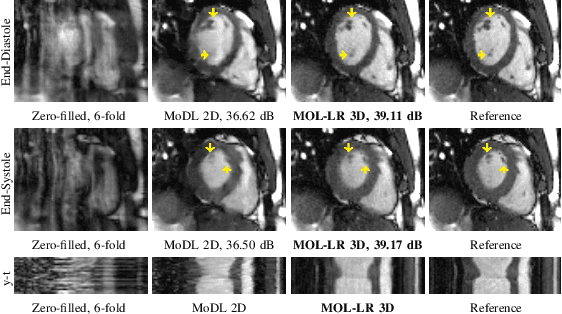

Abstract:Model-based deep learning methods that combine imaging physics with learned regularization priors have been emerging as powerful tools for parallel MRI acceleration. The main focus of this paper is to determine the utility of the monotone operator learning (MOL) framework in the parallel MRI setting. The MOL algorithm alternates between a gradient descent step using a monotone convolutional neural network (CNN) and a conjugate gradient algorithm to encourage data consistency. The benefits of this approach include similar guarantees as compressive sensing algorithms including uniqueness, convergence, and stability, while being significantly more memory efficient than unrolled methods. We validate the proposed scheme by comparing it with different unrolled algorithms in the context of accelerated parallel MRI for static and dynamic settings.